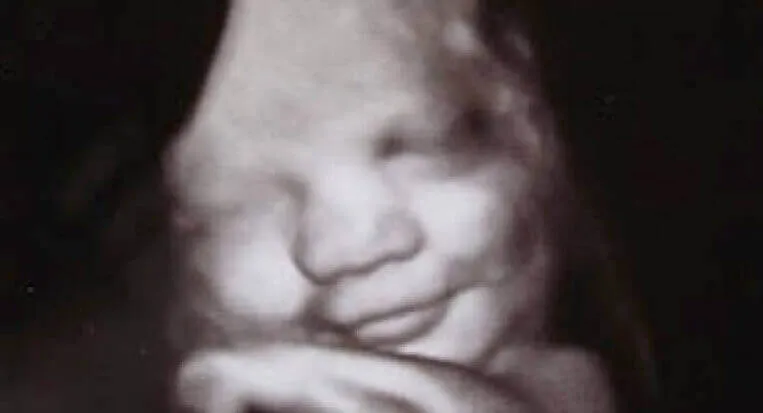

Nedaug sąlygų yra taip apgaubta paslapčių kaip emocijos. Tiesa, kad seksas, kultūra ar kilmės šalis yra mūsų švietimo dalis. Tačiau jie jau yra integruoti į mūsų genetinę bazę. Norėdami tai įrodyti, Durhamo ir Lankasterio (Anglija) universitetai atliko įspūdingą tyrimą, kurio dėka buvo galima įsitikinti, kad vaisiai jau išreiškia nedidelę emocijų įvairovę motinos įsčiose .

Per ultragarsinį skaitytuvą verkė ji veiks kaip veiksminga signalizacijos sistema, nes per ją jis išreikš savo būtiniausius poreikius.